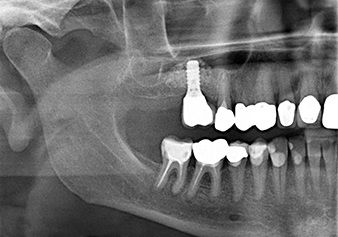

To move the augmentation material in the direction of the maxillary sinus atraumatically, the implant was inserted very slowly by hand (Fig. 9). In the process, the membrane was pushed in the cranial direction once again. After two months, the surgical site healed without irritation. Six months later, the x-ray check showed a significant increase in opacity as an indication of ossification (Fig. 10). The prosthetic restoration was carried out with a metal-ceramic crown.